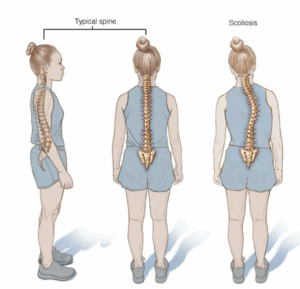

Scoliosis

Scoliosis is a side-to-side curve of the spine. It's most often diagnosed after age 10 or in the early teen years. The spine can curve to either side and in different parts of the back. Experts don't know the cause of most childhood scoliosis.